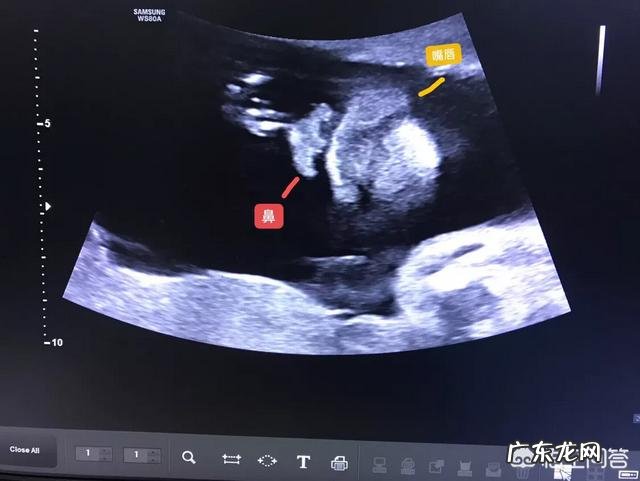

胎儿体位:胎儿位置不好,我们无法观察 。通常对体位要求较高的部位:面部、心脏 。